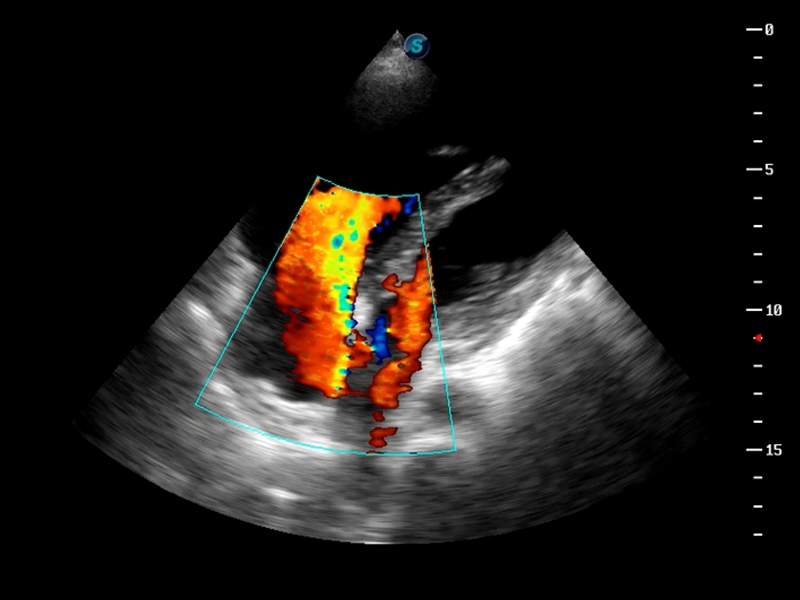

S9便携式彩色多普勒超声诊断仪是新葡的京集团8814检测站研发的高端便携彩超设备,外观设计新颖、产品性能卓越。S9在便携超声领域采用了突破传统的触摸屏交互设计,并以先进的软件硬件技术和设计理念,为您带来清晰的图像质量、稳定的工作性能和便捷的操作体验。

μ-Scan微米成像

脉冲反相谐波成像

TDI组织多普勒成像

AutoC智能血流追踪